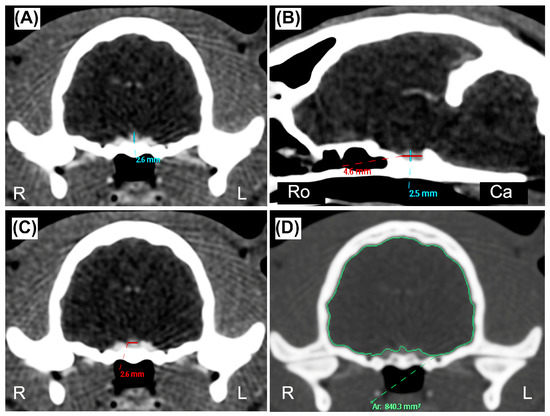

2.3. Data Recording and Image Analysis